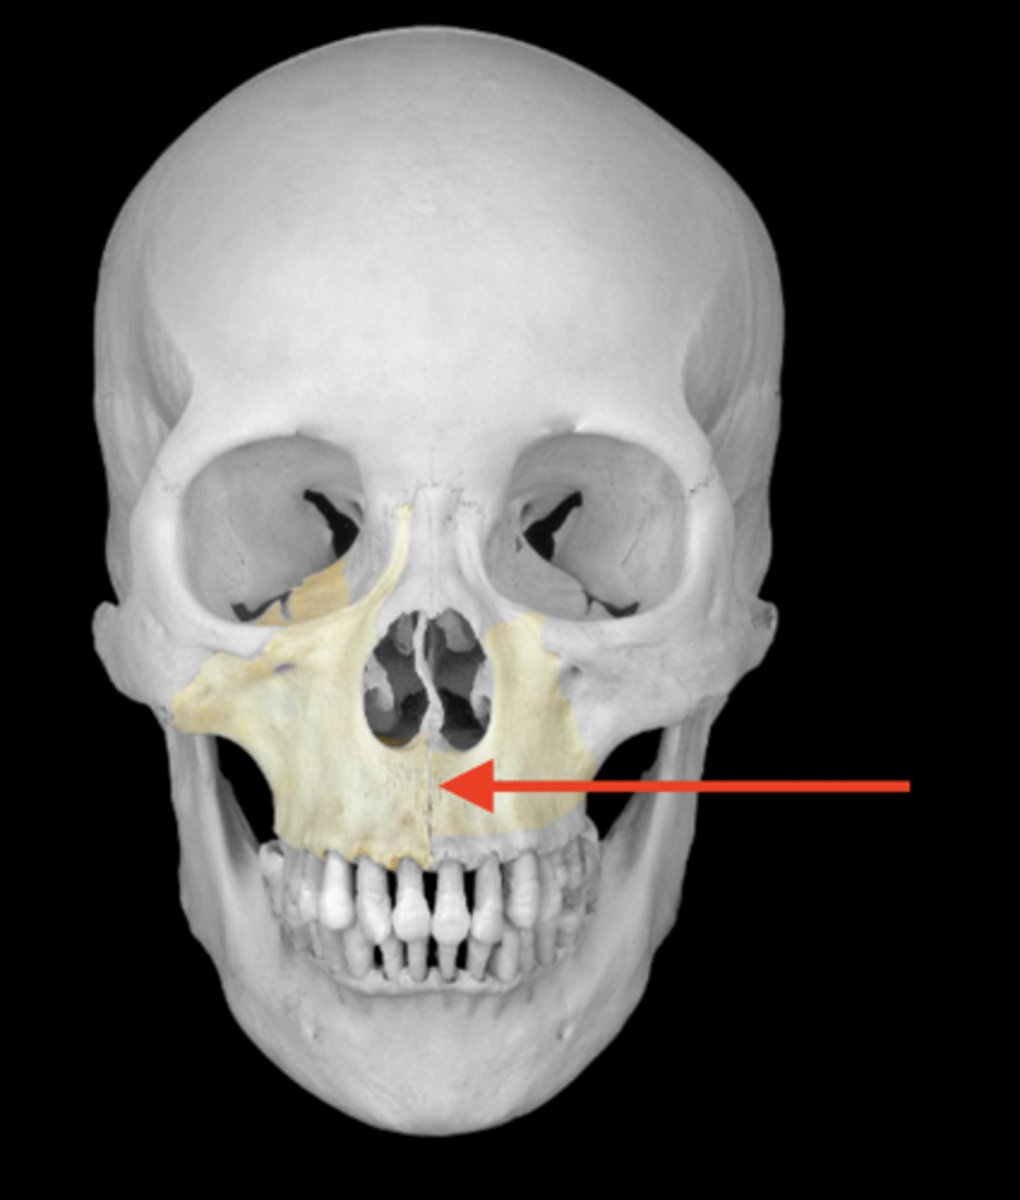

maxilla bone

zygomatic process of maxillae

frontal process of the maxilla

orbital surface of the maxilla

infraorbital margin of the maxilla

infraorbital foramen of maxilla

anterior nasal spine of maxilla